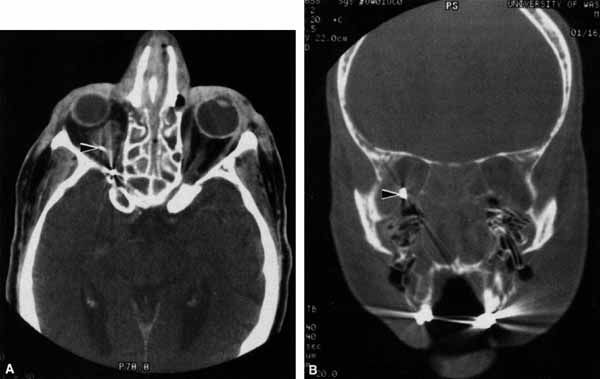

CASE 1 A 70-year-old woman presented with a 6-month history of progressive diplopia and ptosis. She demonstrated complete right third, fourth, and sixth cranial nerve palsies, and hypesthesia of cranial nerve V1 (Fig. 22A). The right pupil was dilated. Computed tomography (CT) disclosed an intracavernous aneurysm (see Fig. 22B). The so-called superior orbital fissure syndrome occurs when an infiltrative, inflammatory, or ischemic event occurs within the superior orbital fissure, but not in the orbital apex.4 A complete superior orbital fissure syndrome occurs when all the neurovascular components passing through the superior orbital fissure are damaged, producing a total ophthalmoplegia, ptosis, and anesthesia of cranial nerve V1 (see Fig. 22A). The pupil may be dilated, miotic, or midposition and fixed, depending on the balance of parasympathetic and sympathetic damage. The superior ophthalmic vein, best seen on CT, may be dilated if venous outflow from the orbit is obstructed. Clues to venous outflow obstruction are increased intraocular pressure, fullness of the upper eyelid, and hyperemia of the deep Tenon's vessels. Ophthalmoscopically, the retinal veins may be dilated. The effect of a lesion in the superior orbital fissure or the anterior cavernous sinus cannot be differentiated clinically (see Fig. 22B). When the posterior cavernous sinus becomes involved, hypesthesia of cranial nerve V2 may also be present. The only difference between a superior orbital fissure syndrome and an orbital apex syndrome is the presence of visual loss caused by optic nerve involvement. Visual acuity, color vision, or the visual field are abnormal. An ipsilateral relative afferent pupil defect is present. CASE 2 A 30-year-old man noted diplopia and right ptosis for the past month. The patient demonstrated normal vision and symmetric pupils but had a neurogenic ptosis (Fig. 23A) and limited right supraduction (Fig. 23B). Otherwise his extraocular movements were full. CT demonstrated an intracranial aneurysm of the posterior communicating artery aneurysm (Fig. 23C). Anatomically, the third cranial nerve branches into its superior and inferior divisions as it enters the orbit through the superior orbital fissure. Superior branch damage results in ptosis (levator muscle) and decreased supraduction (superior rectus muscle). Inferior branch damage results in decreased adduction (medial rectus), decreased infraduction (inferior rectus), decreased excycloduction (inferior oblique), and a dilated pupil (parasympathetic). Anatomically, a cranial nerve III branch nerve lesion seems to imply an anterior cavernous sinus or orbital apex localization. However, functionally, the third cranial nerve may bifurcate in the intracranial portion of the nerve, so cranial nerve III branch nerve palsies have been demonstrated with intracranial lesions. The localizing finding of a cranial nerve III branch nerve lesion is therefore not absolute (see Fig. 23).46 CASE 3 A 12-year-old child was referred by his school nurse because he had been complaining intermittently of double vision and the nurse had noted intermittent right ptosis. The child presented with a right ptosis and limited infraduction of the left eye (Fig. 24A). The ptosis worsened with prolonged up-gaze. A Cogan lid twitch was noted on the right with upward saccades. Injection of 1 mg of edrophonium resulted in complete resolution of diplopia and ptosis (Fig. 24B). The diagnosis was myasthenia gravis. Most orbital and cavernous sinus lesions produce afferent and efferent palsies in an anatomic pattern, for example, the superior orbital fissure has cranial nerves III, IV, VI and V1. When the pareses are not localized anatomically, or when there is variability in findings over time, one should include carcinomatosis or myasthenia gravis (see Fig. 24) in the differential diagnosis. Fatigability and a Cogan lid twitch strongly suggest myasthenia gravis. CASE 4 A 52-year-old woman presented with diplopia when looking to her right. She had noted a red right eye for the past 3 months (Fig. 25A). Visual acuity was 20/20 in both eyes and the pupils were normal. The right eye was limited in abduction. Forced duction testing showed abduction of the right eye to be restricted. Intraocular pressures were 23 mm Hg OD, and 15 mm HG OS. CT showed a dilated right superior ophthalmic vein (Fig. 25B) which was shown to be caused by a dural cavernous fistula. The right medial rectus muscle was also enlarged (Fig. 25C) because of blood engorgement, reducing muscle compliance, which accounted for the restricted abduction. Carotid cavernous fistulas can develop either as a result of trauma or spontaneously.47 A direct carotid cavernous fistula results from a tear in the intracavernous carotid artery with arteriolization of the cavernous sinus and superior orbital vein. Concomitant cranial nerve III, IV, VI, V1 and V2 paresis, elevated intraocular pressure, proptosis, and distention of the deep Tenon's vessels anteriorly (see Fig. 25A) with neuroradiologic evidence of an enlarged superior ophthalmic vein are common (see Fig. 25B). Ophthalmoplegia may also occur on a restrictive basis because of engorgement of the extraocular muscles with blood (see Fig. 25C).36 Dural carotid cavernous fistulas occur where small branches of the intracavernous carotid rupture, allowing access of arterial blood to the cavernous sinus. Typically, the findings are similar to a direct carotid cavernous fistula but of less magnitude. There is no history of trauma, and typically occurs in older persons. However, there is crossover between these two types of carotid cavernous fistula. An excessive ocular pulse tonographically may be helpful in the diagnosis of a carotid cavernous fistula in such cases.48 CASE 5 A 51-year-old woman was referred by her internist for left proptosis. The patient had noted diplopia for the past month but denied blurred vision or pain. Past history was significant for breast carcinoma requiring mastectomy. Vision was 20/20 in both eyes and the pupils were normal. Extraocular movements of the right eye were limited. Forced ductions were restricted. Exophthalmometry readings were 14 mm OD and 18 mm OS (Fig. 26A). CT disclosed a mass encircling the right globe (Fig. 26B). Biopsy disclosed metastatic scirrhous breast carcinoma retracting the right globe.